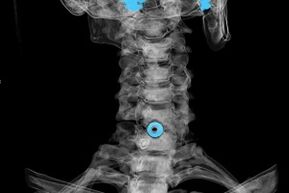

Diagnosing

The diagnosis is established on the basis of characteristic symptoms, as well as using:

- X-rays. The method is ineffective, especially in the last stages of the development of osteochondrosis.

- MRI (magnetic resonance imaging) of the cervical spine.A method that allows you to see bone structures, intervertebral disc herniations, their size and direction of development.

- Computed tomography.A less effective solution than MRI, as the presence and size of the hernia is difficult to determine.

- Doppler ultrasound (to identify pathologies of the vessels of the cervix).This method is used in cases where a blood circulation disorder in the artery is suspected.Using a scan, you can determine the speed of blood flow and whether there are any obstacles to it.